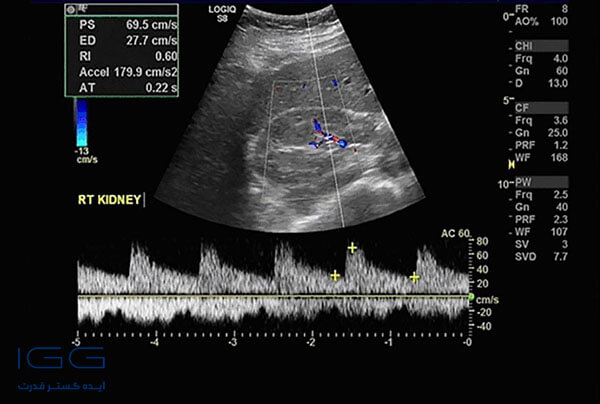

آزمایش رنگی داپلر(کالرداپلر) در بارداری، اختلالات حاملگی و مشکلات مربوط به رگهای خونی را شناسایی میکند. سونوگرافی کالرداپلر به عنوان سونوگرافی بارداری داپلر، داپلر جنینی و USG نیز شناخته میشود. سونوگرافی داپلر در بارداری، جریان خون را از طریق بند ناف و اطراف اندامهای مختلف بدن نوزاد مانند مغز و قلب اندازهگیری میکند.

سونوگرافی داپلر همچنین نشان میدهد که بارداری پرخطر یا کمخطر است. این آزمایش میتواند سرعت جریان خون را با اندازهگیری میزان تغییر در فرکانس آن به صورت تقریبی نشان دهد. سونوگرافی داپلر یک روش بدون درد و غیر تهاجمی (بدون جراحی یا برش) است که در آن از احتمال هر نوع اختلال بارداری یا نارسایی جنین مطلع خواهید شد.

در حین انجام اسکن بارداری داپلر، تکنسین از شما میخواهد که روی میز معاینه دراز بکشید. سپس یک ژل روی پوست قسمت مورد نظر در معرض دید پخش می کند. در این مرحله یک مبدل روی ناحیهای که ژل پخش شده است، قرار میگیرد. سپس مبدل دستگاه، امواج صوتی را به داخل بدن میفرستد. امواج صوتی داپلر ضبط و به صورت تصویر یا گرافیک نشان داده خواهد شد. پس از اتمام تصویربرداری، میتوانید ژل را از روی پوست خود پاک کنید. در سونوگرافی داپلر نتیجه 30 تا 60 دقیقه بعد از تصویربرداری به شما تحویل داده میشود. سپس دکتر فیلم و الگوی تغییرات موج را تفسیر خواهد کرد.